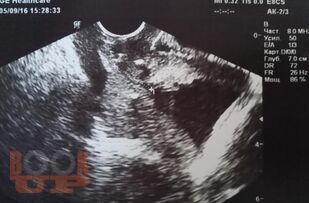

Методические рекомендации посвящены особенностям ведения беременных с истмико-цервикальной недостаточностью и пролабированием плодного пузыря. Представлен обзор зарубежных и отечественных представлений об этиопатогенезе, методах диагностики ИЦН. В методических рекомендациях подробно описана методика хирургической коррекции при пролабировании плодного пузыря, представлен иллюстрационный материал об этапах операции, а также имеется информация об особенностях предоперационной подготовки и введения в послеоперационном периоде. Представлены данные о возможности прогнозирования развития ИЦН на амбулаторном этапе вне беременности. Рекомендации содержат рисунки, таблицы, тестовые задания и ситуационные задачи. Методические рекомендации предназначены для врачей акушеров-гинекологов.